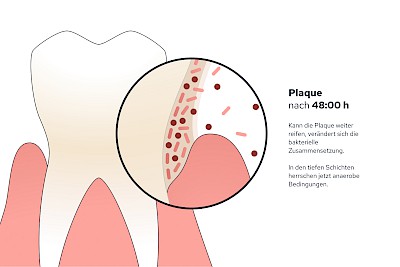

Plaque (Biofilm)

Als Plaque bzw. Biofilm bezeichnet man die Gesamtheit aller Mikroorganismen (Mikrobiom) auf der Zahnoberfläche. Werden die Zähne nicht geputzt, haften die Beläge nach 24 Stunden bereits so fest, dass diese mit der Zahnbürste schon nicht mehr vollständig entfernt werden können.

Im Anfangsstadium kann Plaque (Biofilm) durch Optimierung und Intensivierung der Mundhygiene (Zähneputzen mit Zahnpasta) noch reduziert werden. Lassen sich die Beläge mit Zahnbürste und Zahnpasta nicht mehr entfernen, muss der Zahnarzt unterstützen.